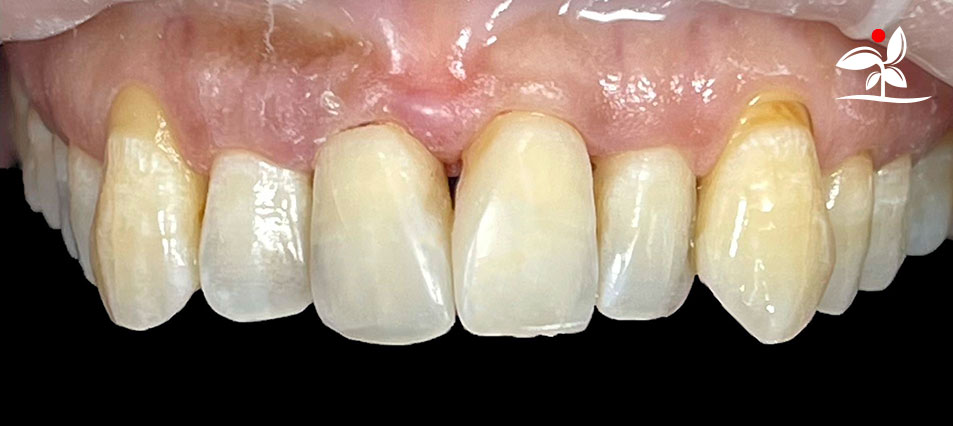

Restoration of Class IV Lesions using Naturomimetic Layering Technique (NLT) and Bioactive Restorative Materials

Dr Aung Pyae Phyo, Myanmar

include the methods of treatment that are simple, fast, predictable and healthy. In aesthetic restoration, the tooth color restorative materials placement technique is one of the most challenging, confusing and frustrating areas to learn owing to the multiple techniques that have been proposed by many clinicians and replicating such techniques in practice is not always as easy as they are marketed in dentistry. Natural teeth are complex in structure and hard to simulate due distribution of colors through enamel and dentin [2]. Aesthetic restoration strategies should follow proper understanding of defects, right selection of restorative materials along with their proper application, finishing, texturing and polishing [2].